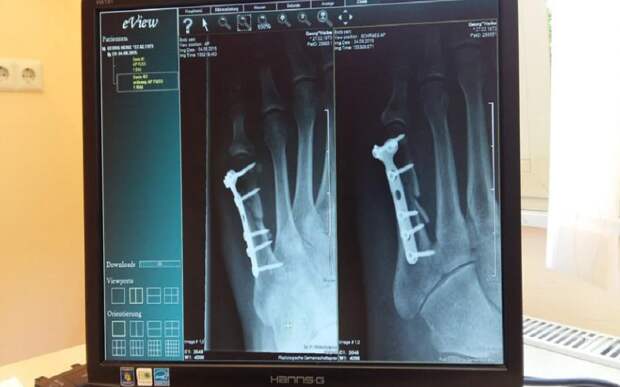

Рентгено-диагностический комплекс медучреждение получило по программе модернизации первичного звена здравоохранения. Он позволяет делать более точные снимки, к тому же врачам удобнее с ними работать.

Пациенты получают меньшую дозу излучения при обследовании.«Теперь мы имеем современный цифровой рентгеновский аппарат на два рабочих места и можем проводить исследования костей и суставов, придаточных пазух носа, легких, органов мочевой системы, – оценил возможности нового комплекса заведующий рентгенологическим отделением Рязанского кардиодиспансера Руслан Хашумов.